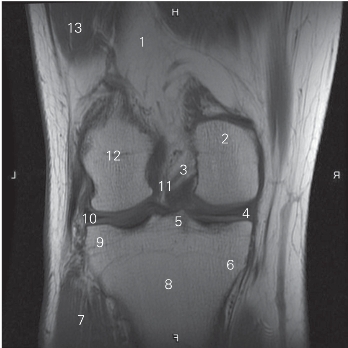

图5-29 经前后交叉韧带的冠状断层MR T1加权图像

1 股骨 femur 2 股骨内侧髁 medial condyle of femur

3 后交叉韧带 posterior cruciate ligament

4 内侧半月板 medial meniscus

5 胫骨髁间隆起 intercondylar eminence of tibia

6 胫骨内侧髁 medial condyle of tibia

7 腓肠肌外侧头 lateral head of gastrocnemius

8 胫骨 tibia 9 胫骨外侧髁 lateral condyle of tibia

10 外侧半月板 lateral meniscus

11 前交叉韧带 anterior cruciate ligament

12 股骨外侧髁 lateral condyle of femur

13 股外侧肌 vastus lateralis